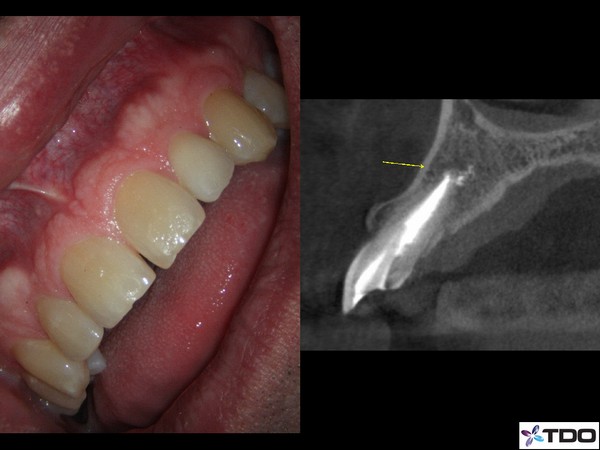

Retreatment and Repair

This patient fractured her front tooth.  The crown was only 2 years old.  Extraction and implant placement was recommended.  It would have been a challenging case esthetically.  We were able to retreat the contaminated root canal.  Posts were placed for reinforcement.  We were able to use the existing crown by retrofitting it.  We managed the occlusion to mitigate the risk of future fracture.